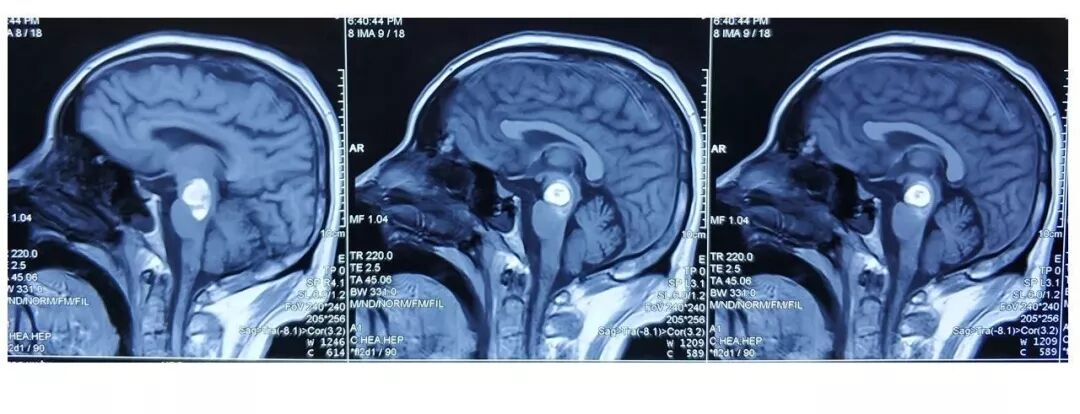

术后患儿情况:

目前患者恢复良好,偶有头痛,无颅内感染,无再发抽搐,出院后未服用抗癫痫药物。